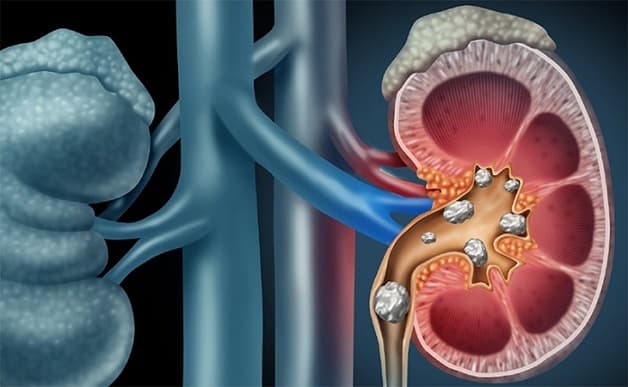

Bàng quang hay còn gọi là bọng đái là nơi chứa nước tiểu do thận tiết ra trước khi thoát ra ngoài bằng cách đi tiểu. Sỏi bàng quang xuất hiện do sự tích tụ của các khoáng chất. Sỏi thường có hình tròn, ít xù xì. Đàn ông là đối tượng có nguy cơ mắc bệnh nhiều hơn phụ nữ.

Khi sỏi rơi xuống bàng quang, nếu là sỏi nhỏ có thể được thải ra ngoài qua đường tiểu, các viên sỏi lớn không thể đưa ra ngoài sẽ nằm tại bàng quang và tích tụ lớn dần do các cặn sỏi ở trong bàng quang bám vào gây ra cơn đau.

Bệnh sỏi bàng quang có thể do sỏi từ thận, tiết niệu rơi xuống

2.1. Sỏi từ các cơ quan trong hệ tiết niệu

Sỏi không phải lúc nào cũng hình thành từ bàng quang. Một số trường hợp xuất hiện sỏi niệu quản, sỏi thận rơi xuống bàng quang.